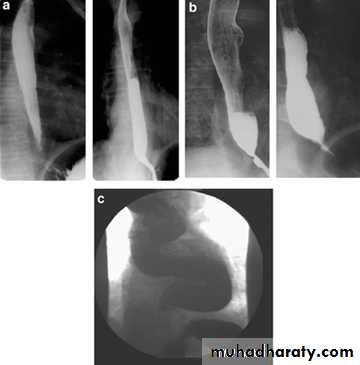

Narrowing :

1-the narrowing is Constant Short length (confined to cardia).

2-Regular and smooth.

3- No shouldering sign.

4-Tapering (Tip of pencil , cigar shape) Under left dome of diaphragm.

Achalasia continue

5. DILATATION (Sac like in proximal part )6-Undulating or spiky out line due to sluggish peristalsis.

7 Non- homogeneity of Barium due to food particles.

8-Air Barium level.

9- CXR shows widening of mediastinum.

10-Absence of fundal gas shadow.

7-Basal fibrosis in lungs due to repeated aspiration pneumonia .